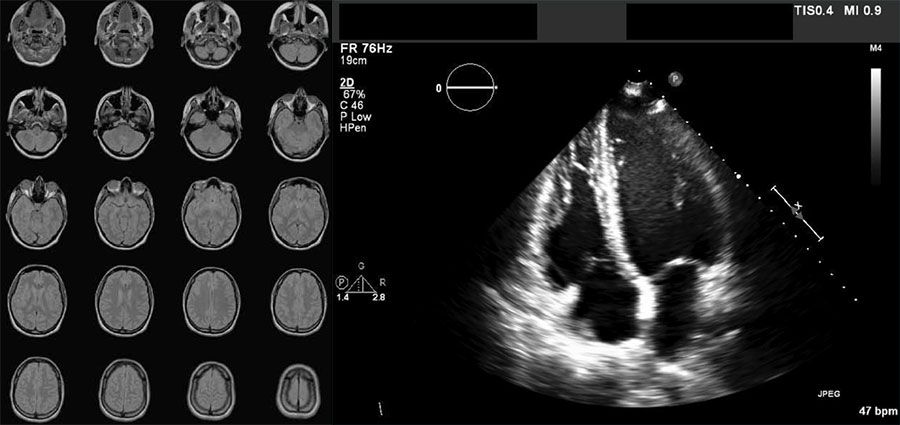

Exemples d'images au format DICOM : une série de 20 images issues d'une IRM cérébrale et une échographie cardiaque.

Série d'images cérébrales obtenues par IRM (à gauche) et échographie cardiaque (à droite), stockées au format DICOM.